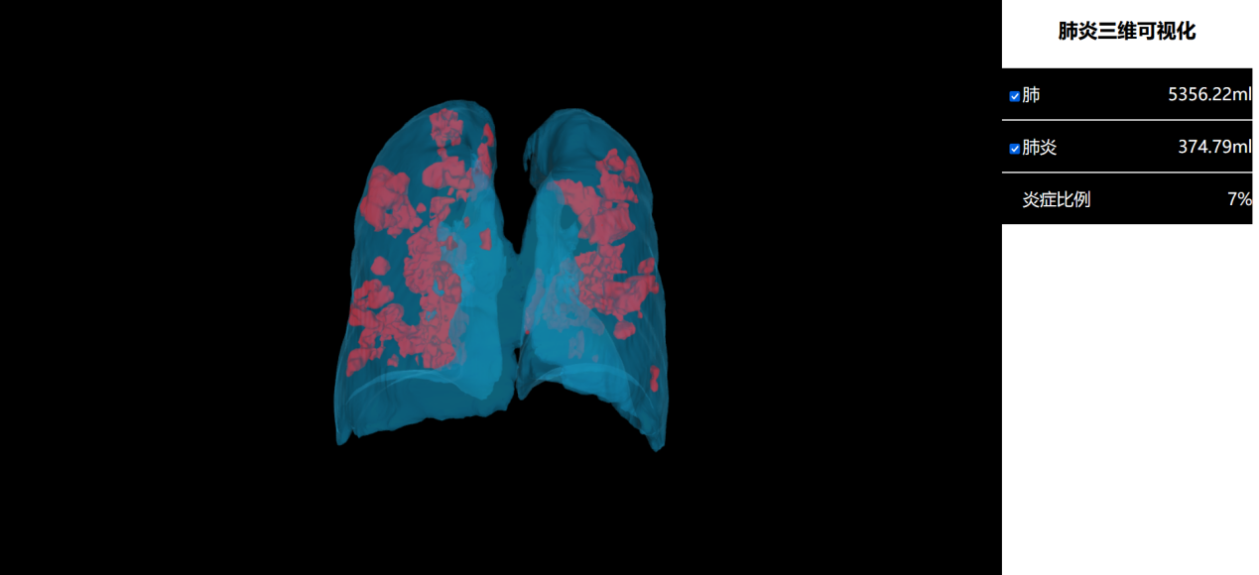

该成果研究了高精度快速多期新冠肺炎患者几何模型构建和定量分析算法,研究成果发表在医学影像顶级期刊TMI(IEEE TRANSACTIONS ON MEDICAL IMAGING,IF:10.048)上。目前该系统已经应用在张家界人民医院、哈尔滨医科大学附属第一医院等多家医院。经过科学对比和分析,该系统能够较好实现2分钟内多期新冠肺炎患者肺部器官和病灶的快速识别,并实现三维可视化,时间效率较目前常用影像建模软件提升30倍。极大提升了医生诊断的工作效率,同时能计算出肺炎体积,并进行定量分析,作为诊断的参考依据。该系统还能够支持多期医学影像数据协同管理,多人多机协同操作。